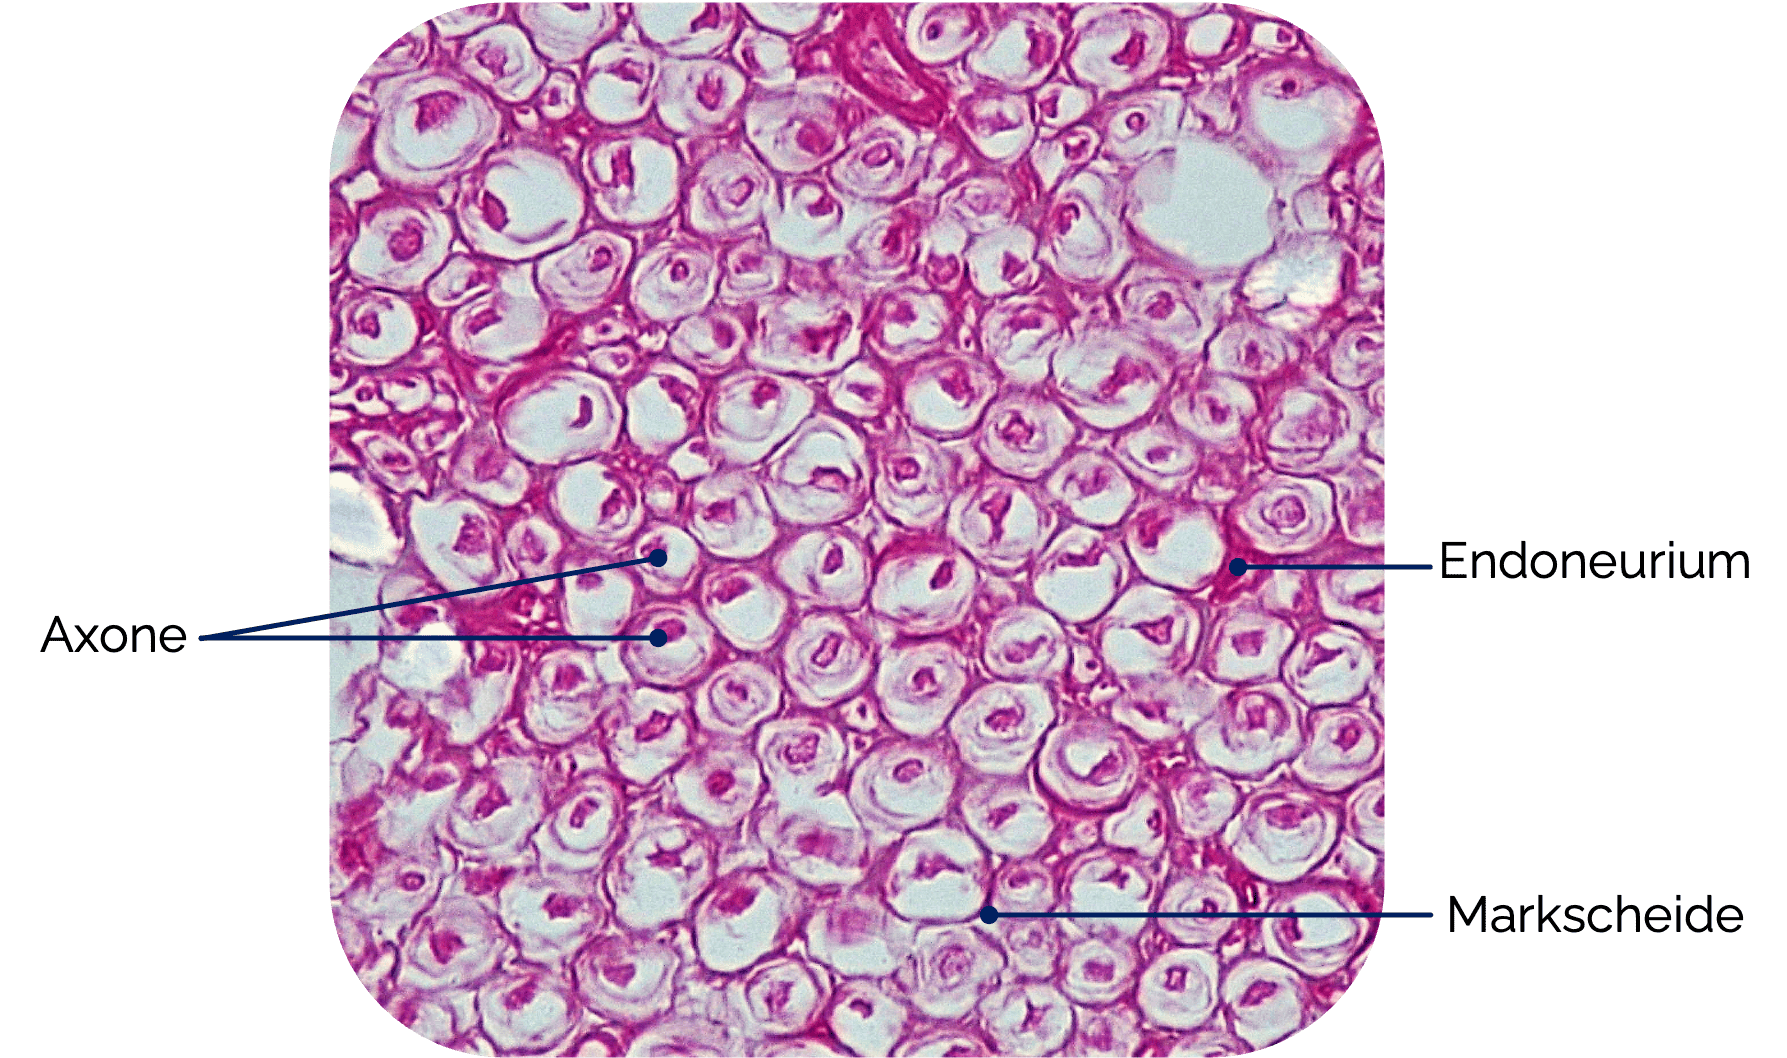

Peripherer Nerv im Querschnitt:

Nervenfasern setzen sich aus Axonen und ihren Markscheiden zusammen

Endoneurium

Umgibt jede einzelne Nervenfaser

Das Endoneurium bildet zusammen mit der Basalmembran der Schwann- Zelle die Endoneuralscheide